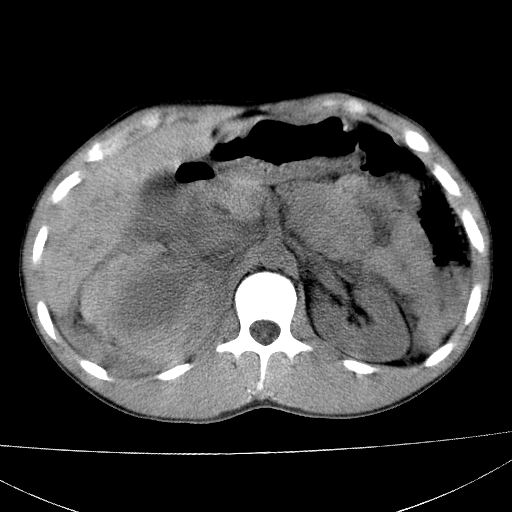

标题: CT15860:男,21岁,腹部外伤2小时伴胸疼。 [打印本页]

标题: CT15860:男,21岁,腹部外伤2小时伴胸疼。

肝脏及肾脏明显有损伤性改变并激发腹腔内积液(血),以肝脏撕裂及肾周积血显著。

1)肝破裂伴腹腔积液(血)。2)右肾破裂伴右肾包膜下及肾周血肿。3)腹部空腔脏器穿孔可能。4)右侧少量胸腔积液(血)。

肝肾挫裂伤,右肾周及包膜下血肿,腹腔积液,不排除空腔脏器穿孔,建议行增强检查

肝、右肾包膜下血肿,右侧腰大肌及腹膜后血肿;腹腔少量积血;腹腔疑有少量游离气体伴肠破裂。

肝右肾挫裂伤,右肾包膜下及肾周血肿.胸腹腔少量积液.脾脏下部密度稍不均,必要时,增强.

1肝挫伤伴腹腔积液。2右肾挫裂伤伴右肾包膜及肾后间隙肿血肿。3右肾脏周围的积气,十二指肠显示结构不清,考虑十二指肠降部破裂可能性大。